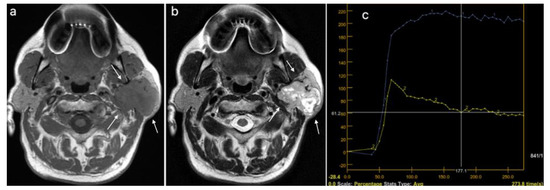

| MRI, T1 weighted image, n (%) | 0.272 | ||

| Hyperintense signal | 9 (16.67) | 1 (9.09) | |

| Mixed signal intensity | 16 (29.63) | 1 (9.09) | |

| Hypointense signal | 29 (53.7) | 9 (81.82) | |

| MRI, T2 weighted image, n (%) | 0.004 | ||

| Hyperintense signal | 17 (31.48) | 0 (0) | |

| Mixed signal intensity | 27 (50) | 4 (36.36) | |

| Hypointense Signal | 10 (18.52) | 7 (63.64) | |

| DCE MRI*–TIC curve+, n (%) | 0.382 | ||

| Type A | 16 (29.63) | 1 (9.09) | |

| Type B | 18 (33.33) | 5 (45.45) | |

| Type C | 20 (37.04) | 5 (45.45) | |

| DCE MRI, TIC curve grouped (A, B vs. C), n (%) | 34 (62.96) | 6 (54.5S5) | 0.737 |

| DCE MR, TTP (ms), median (IQR) | 133.5 (87.15–203.75) | 143 (138–204.45) | 0.113 |

| DWI MRI, ADC × 10−3 mm2/s, median (IQR) | 1.03 (0.8–1.44) | 0.78 (0.68–0.99) | 0.024 |